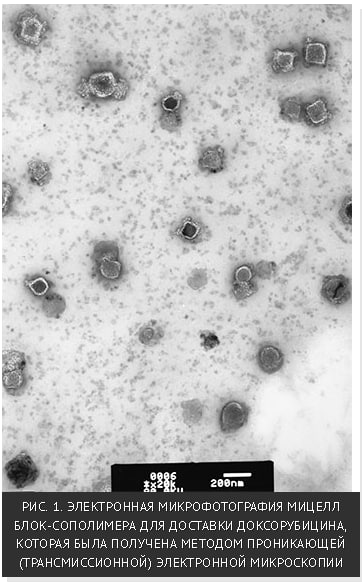

"И, наконец, ещё один «пассажир» наноносителей, разработанных группой профессора Татьяны Желтоножской – наночастицы серебра очень малого размера (2-8 нм), синтезированные прямо в мицеллоподобных структурах (рис. 3).

Защищённое мицеллярной "короной" наносеребро не темнеет на свету и сохраняет свои свойства в водном растворе в течение как минимум двух лет. Это – биоцидный препарат или, как говорят сегодня, "наноантибиотик" нового поколения. Он эффективен в производстве перевязочных и гигиенических материалов, дезинфекции и заживлении ран в госпиталях и одежды военных в полевых условиях."